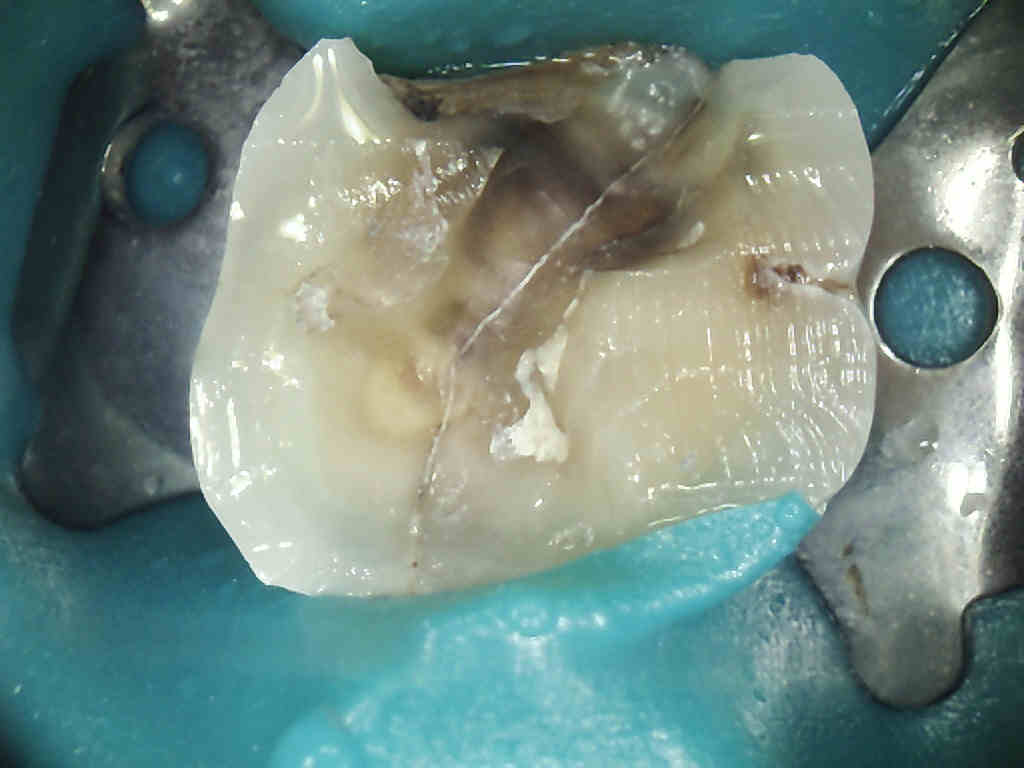

![]() |

| Here looks like MB1 continues around curve |